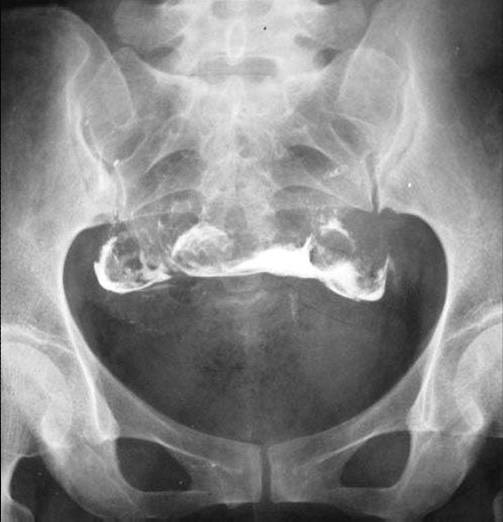

照片名称:子宫输卵管造影3

照片名称:子宫输卵管造影4

照片名称:子宫输卵管造影2

照片名称:子宫输卵管造影1

照片名称:子宫输卵管造影